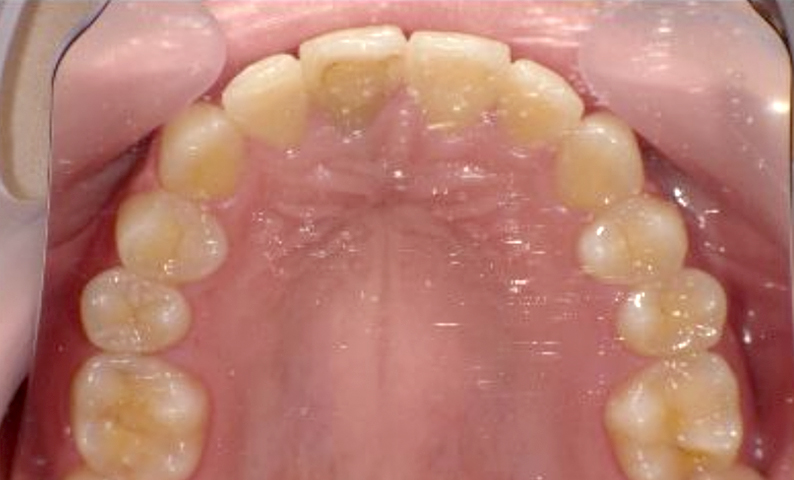

症例_018 上顎だけの部分矯正

治療期間:7ヶ月金額:30万円+税女性前歯のガタガタ上の前歯だけ

| Before | After |

|---|---|

|